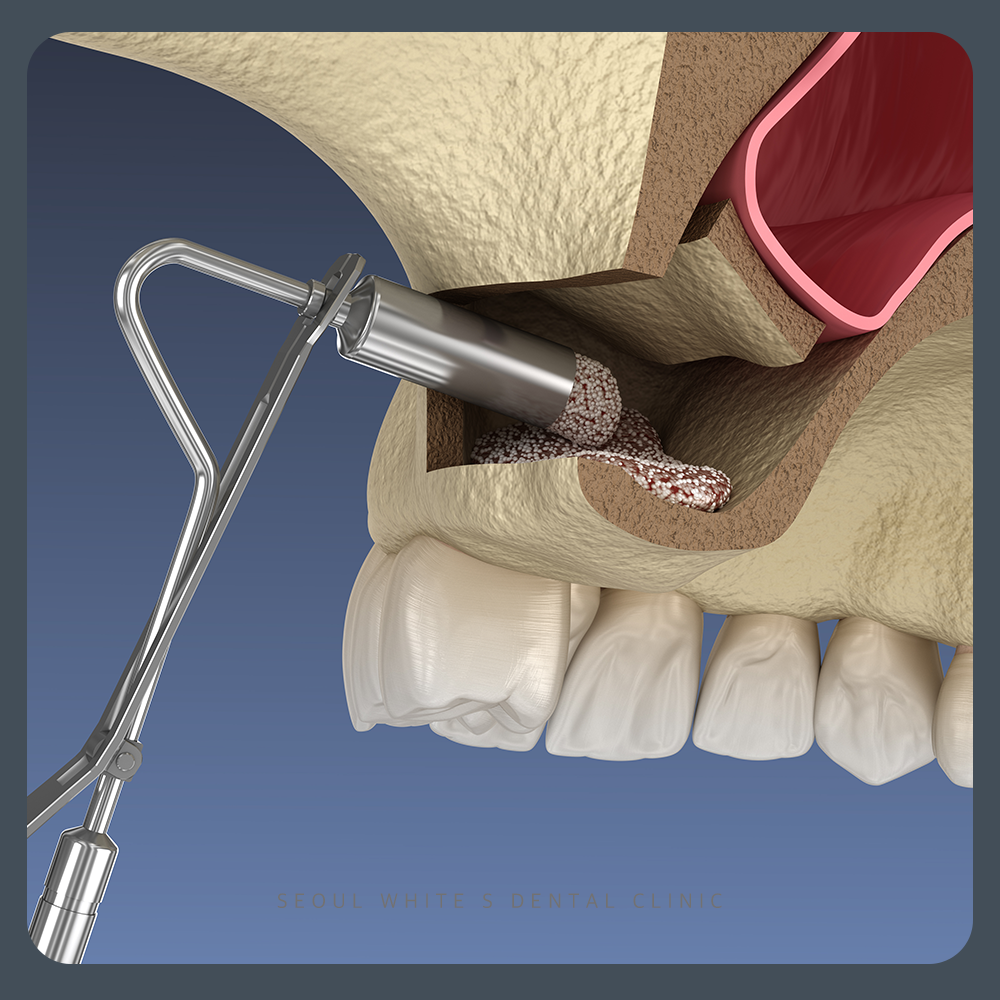

상악동거상술은 위턱 어금니 뒤쪽에 위치한 ‘상악동’이라는 빈 공간을 위로 들어 올려 인공뼈를 채워주는 수술입니다. 일반적으로 위턱 어금니 부위는 치아가 빠진 후 시간이 지나면 뼈가 얇아져 임플란트를 심기 어려운 경우가 많습니다. 이때 상악동거상술을 통해 뼈의 두께를 확보하면, 임플란트 시술이 가능해집니다. 다양한 임플란트 경험을 보유한 의료진이 있는 경우, 안전하게 수술을 진행할 수 있습니다.

또한 상악동 거상술을 고려하여 뼈의 잔존 두께를 측정한 결과, 5mm 이상으로 확인되었습니다. 이는 환자분이 증상을 방치하지 않고 적절한 시기에 내원해주신 덕분에 뼈가 충분히 보존된 모습을 볼 수 있습니다. 따라서 불필요하게 측방접근법을 사용할 필요 없이, 현재 조건에서 충분히 가능한 상방접근법을 적용하여 수술을 진행할 수 있었습니다.